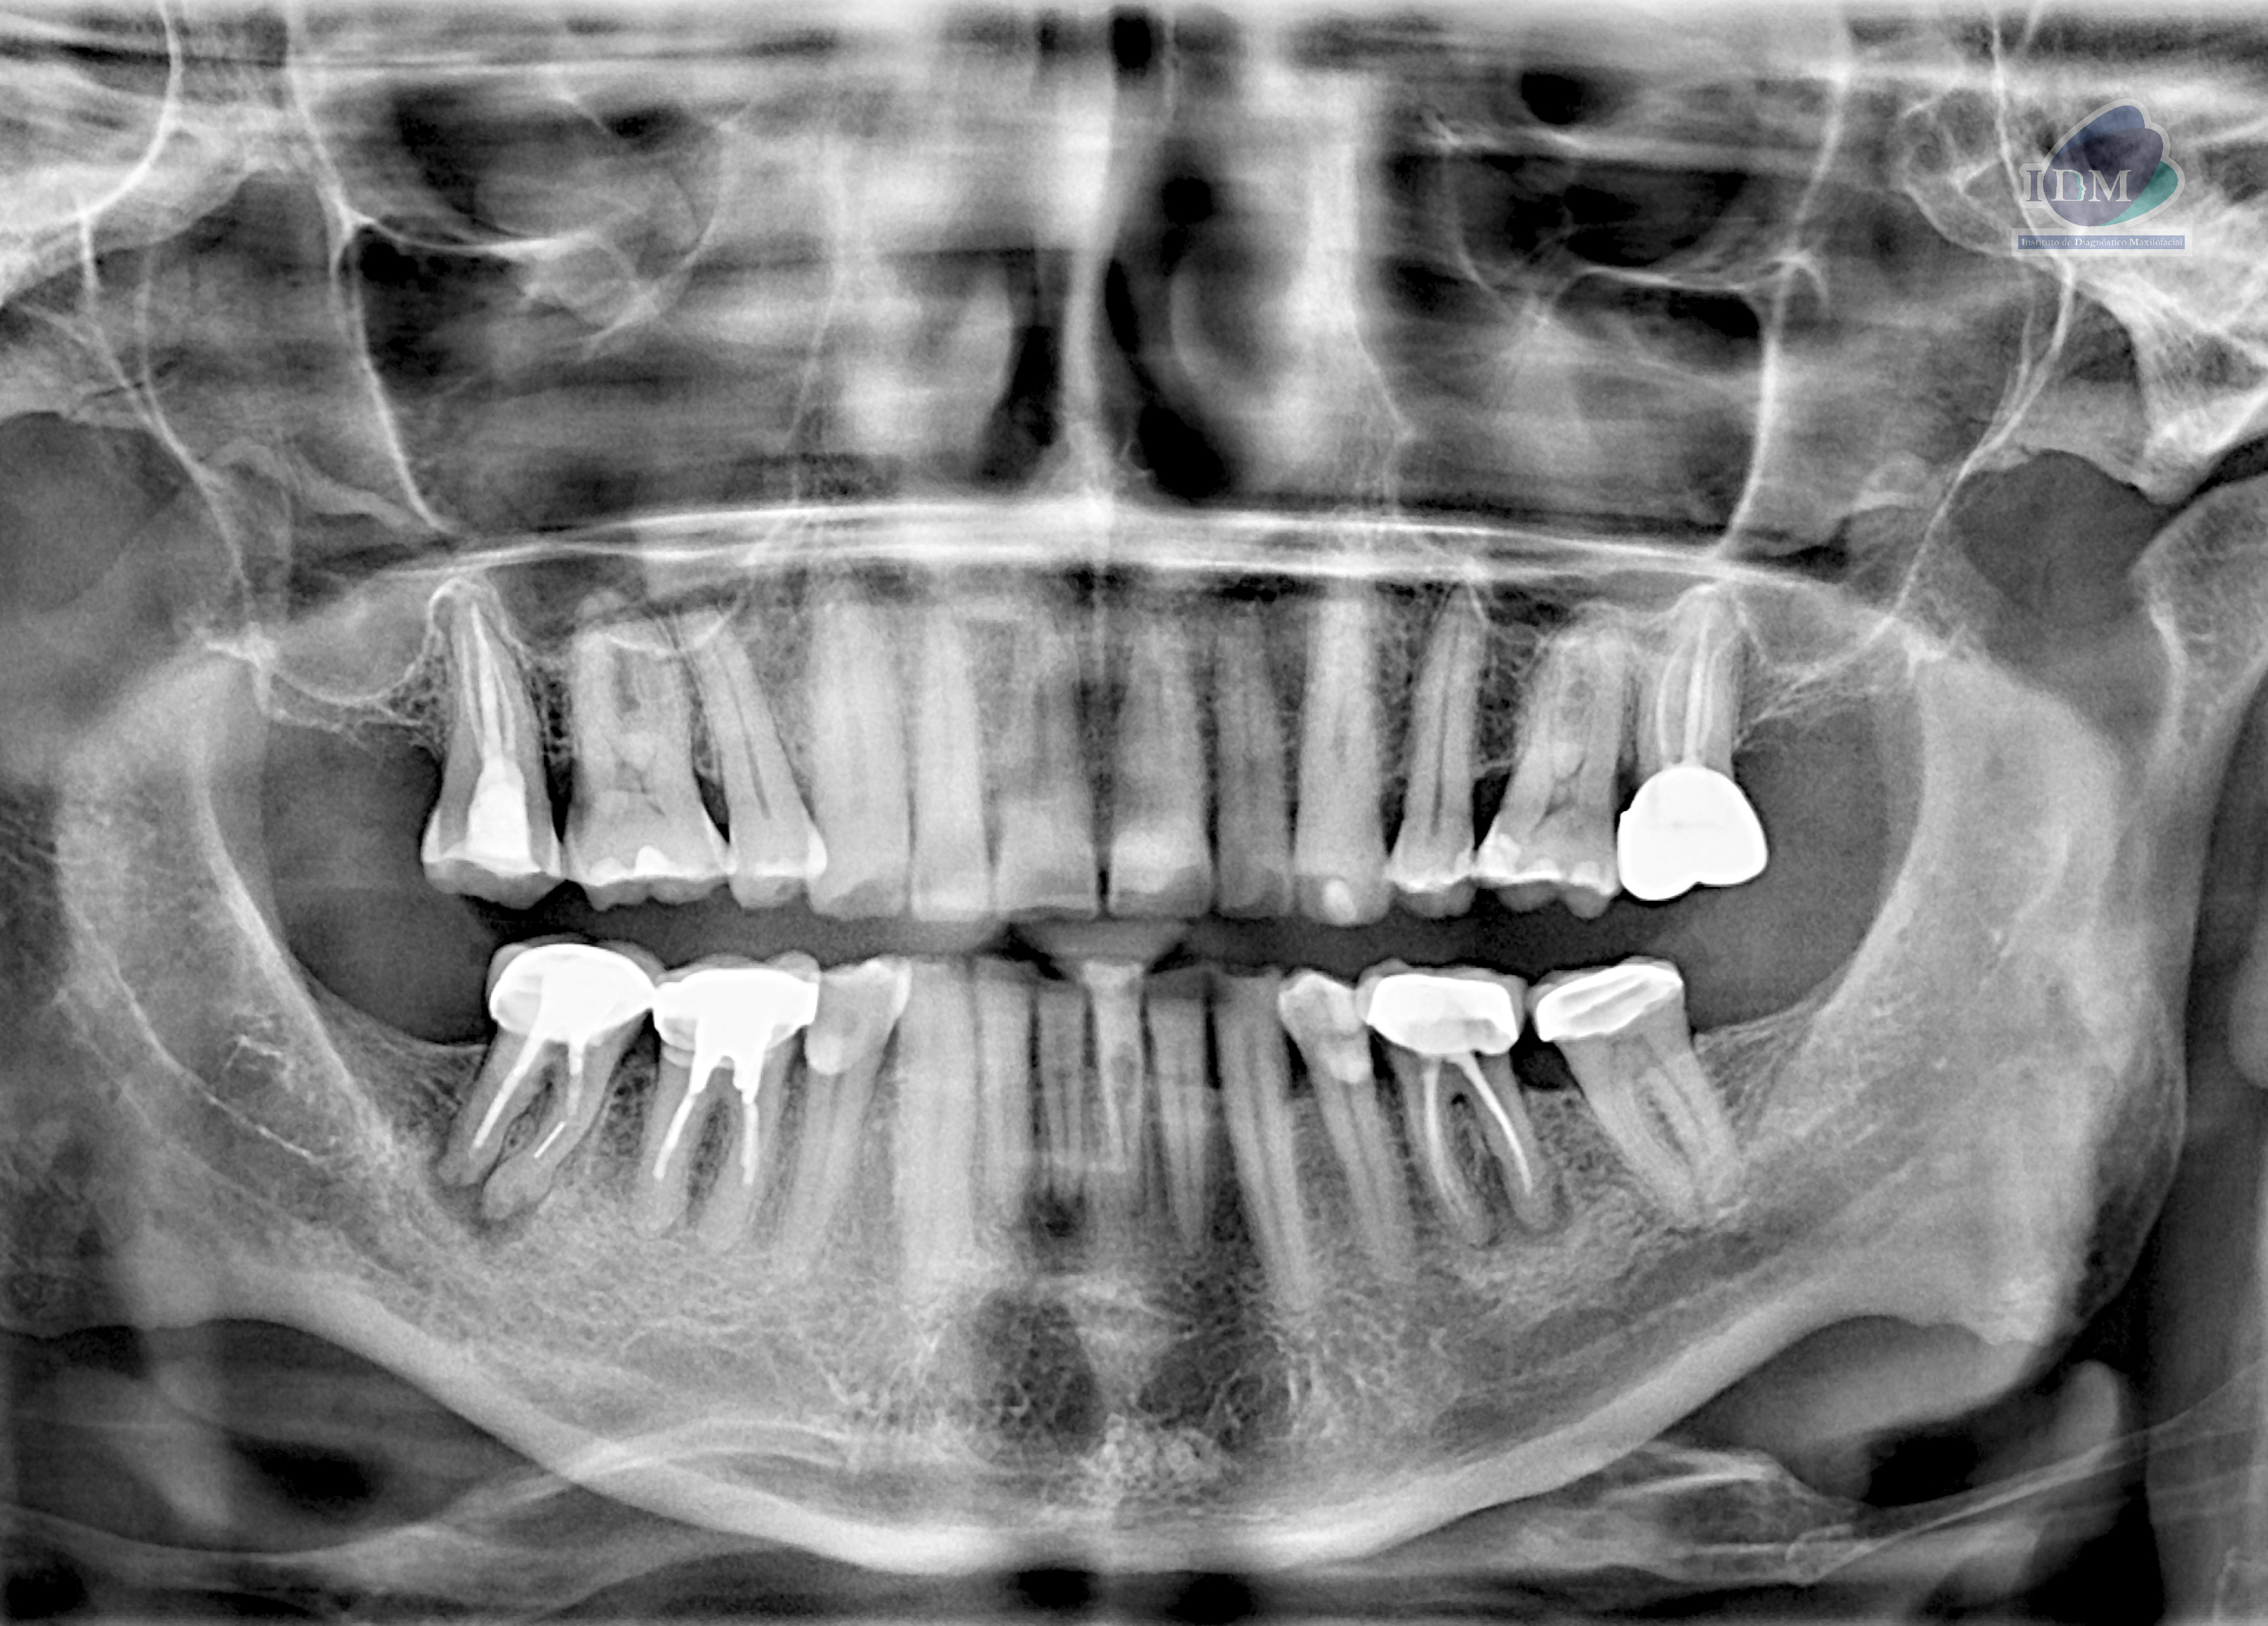

Radiografia Panorámica

A la evaluación de la radiografía panorámica se observan aplanamiento del contorno condilar bilateral, neumatización alveolar de ambos senos maxilares, múltiples coronas protésica, obturación de conductos, así como la presencia de procesos osteolítico periapicales en las piezas 36 y 46; esta última con presencia de una imagen radiopaca en raíz mesial compatible con fragmento de instrumento endodóntico. Finalmente se observa la pieza 41 con un proceso osteolítico periapical y la pieza 31 con una imagen radiolucida proyectada a nivel de tercio cervical.